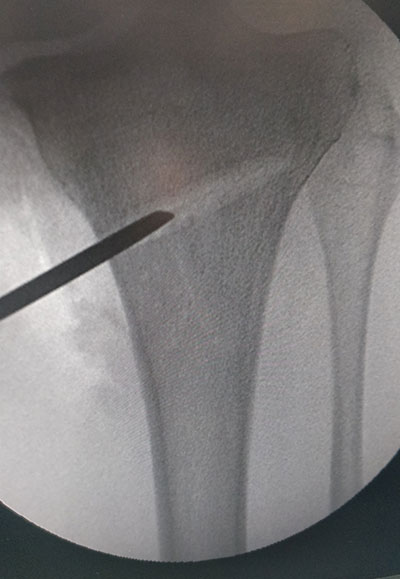

STEPS OF HTO